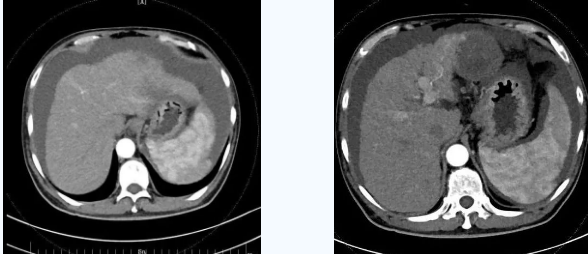

術(shù)后一個(gè)月秦先生來(lái)院復(fù)查,腹水已明顯較前減少,精神和飲食較術(shù)前明顯好轉(zhuǎn)。

韓國(guó)宏院長(zhǎng)介紹,TIPS原理是采用特殊的介入治療器械,在X線(xiàn)透視導(dǎo)引下,經(jīng)頸靜脈入路,建立肝內(nèi)的位于肝靜脈及門(mén)靜脈主要分支之間的人工分流通道,并以金屬覆膜內(nèi)支架維持其永久性通暢,達(dá)到降低門(mén)脈高壓后減少腹水產(chǎn)生,控制和預(yù)防食道胃底靜脈曲張破裂出血的目的。